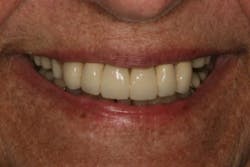

There was some fine-tuning to the patient's occlusion during the healing period. Nevertheless, the goals of treatment were accomplished very predictably. Figures 21 (horizontal position) and 22 (vertical position) verify both the new vertical and horizontal positions of the upper incisal edge.

Understanding the patient’s masticatory system requires the dentist to gather the correct data through a comprehensive examination. (6) In addition, diagnostic records (mounted models in centric relation and digital photography) can be used to provide predictable results. The overall esthetic outcome, along with improved function, gave the patient a new outlook on life and increased confidence—all within her budget (figures 23–25). The Dawson Academy is a great resource for learning about the masticatory system, functional esthetics, and a predictable treatment-planning protocol.